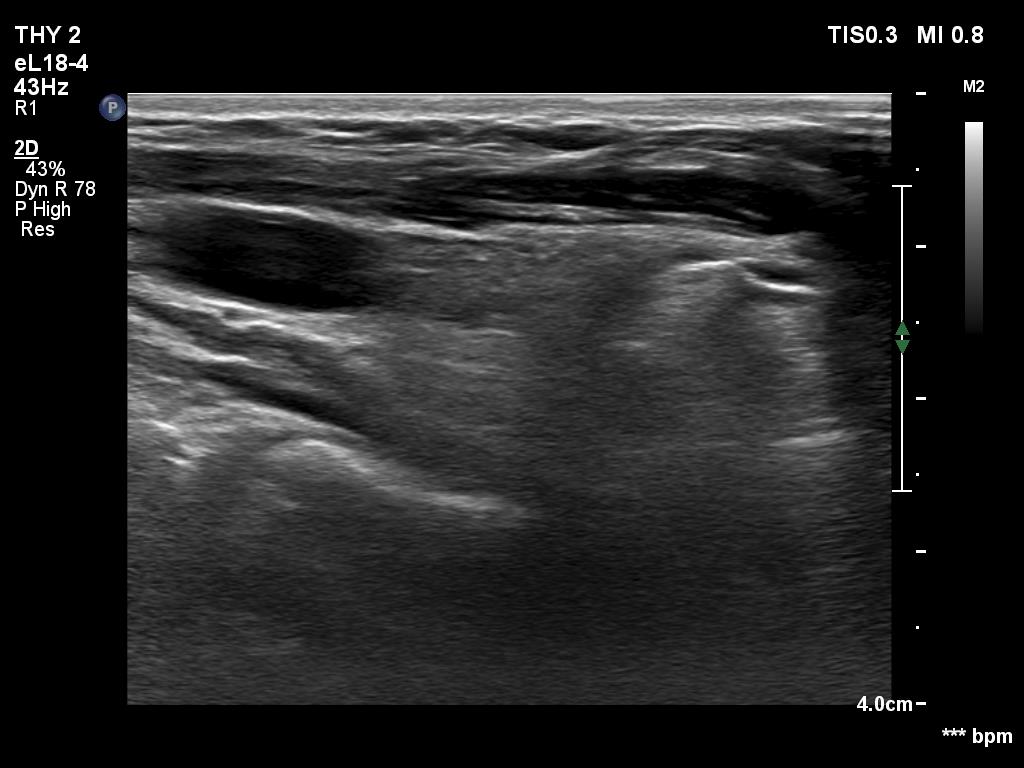

Ultrasonography. The right lobe was replaced with connective tissue. A hypoechoic mass was found in the left thyroid bed. On certain sections, this mass was very similar to a muscle fiber, however some other sections proved the presence of intralesional echogenic figures; the presence of back wall cystic figures was obvious but in the event of some granules microcalcifications should be considered. The lesion was vascularized, which excluded that the mass is muscle fiber.